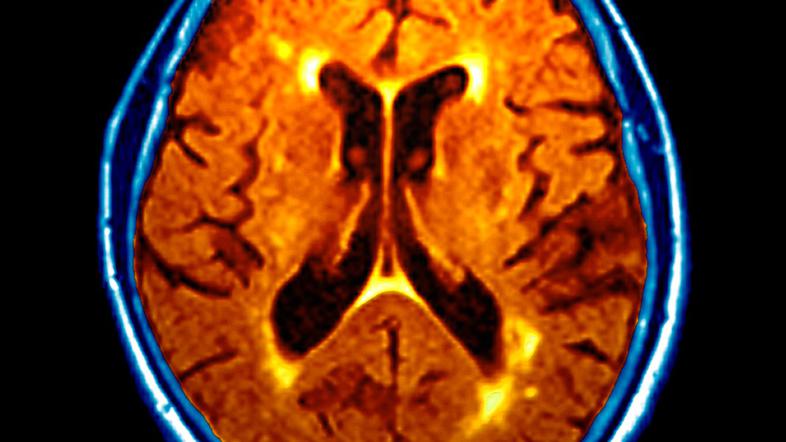

Če imate grdo navado, da si vrtate po nosu, ne gre podcenjevati najnovejše raziskave avstralskih znanstvenikov. Ti so ugotovili presenetljivo in nenavadno povezavo med tem početjem in Alzhajmerjevo boleznijo.

Raziskava objavljena v prestižni reviji Nature je namreč pokazala, da se lahko bakterija klamidija (Chlamydia trachomatis)  ki je običajno prisotna v nosu, prikrade v možgane in sproži niz dogodkov, ki lahko vodijo do Alzheimerjeve bolezni.

Raziskovalna skupina je izvedla obsežne raziskave na miših, kjer se je pokazalo, da lahko bakterije potujejo po vohalnem živcu.  Okužba povzroči odlaganje beljakovine beta-amiloida v obliki netopnih plakov, ki jo v znatnih količinah najdejo pri ljudeh z Alzheimerjevo boleznijo. "Prvi smo dokazali, da lahko bakterija klamdija preide neposredno v nos in v možgane, kjer lahko sproži patologije, ki so videti kot Alzheimerjeva bolezen," je pojasnil nevroznanstvenik James St John z univerze Griffith v Avstraliji. "Videli smo, da se to dogaja pri miših, in dokazi so lahko zastrašujoči tudi za ljudi," je dejal.

Raziskovalci pod vodstvom znanstvenikov z avstralske univerze Griffith so izvedli teste z bakterijo, imenovano Chlamydia pneumonia, ki lahko povzroči pljučnico, in zanimivo, našli so jo v večini človeških možganov, prizadetih zaradi pozne demence.